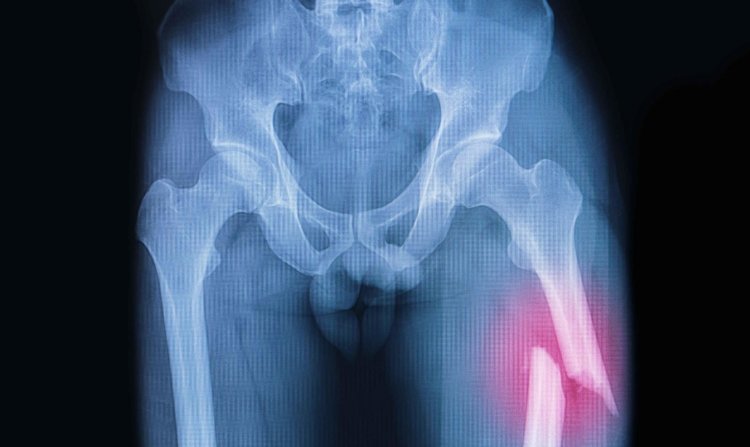

Риск переломов костей выше почти в два раза

Согласно результатам исследования, которое было проведено британскими учеными, у вегетарианцев риск получения переломов повышен на 43%. Подробности опубликованы в журнале BMC Medixine.

Перелом бедренной кости у вегетарианцев случается более чем в два раза чаще, чем у людей, которые едят мясо

В исследовании приняли участие почти 55 тысяч человек, за которыми исследователи наблюдали в течение 18 лет. Среди них 15 499 были вегетарианцами, а 1982 — веганами. Как не сложно догадаться, чаще всего от переломов страдали участники, отказавшиеся от мяса. Причем переломы бедренных костей у них случались более чем в два раза чаще, чем у людей, которые ели мясо. Кроме того, у вегетарианцев и веганов чаще возникали переломы ключицы, ребер и позвонков.